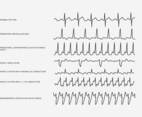

- heart beat

- medical

- fitness

- health